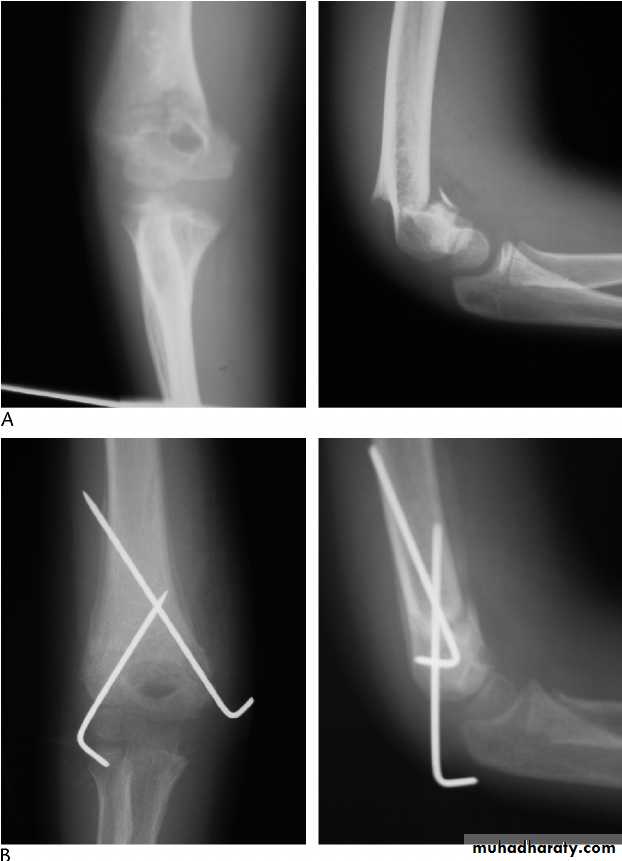

40 years male fall on out streched hand

Radial nerve palsy after reduction